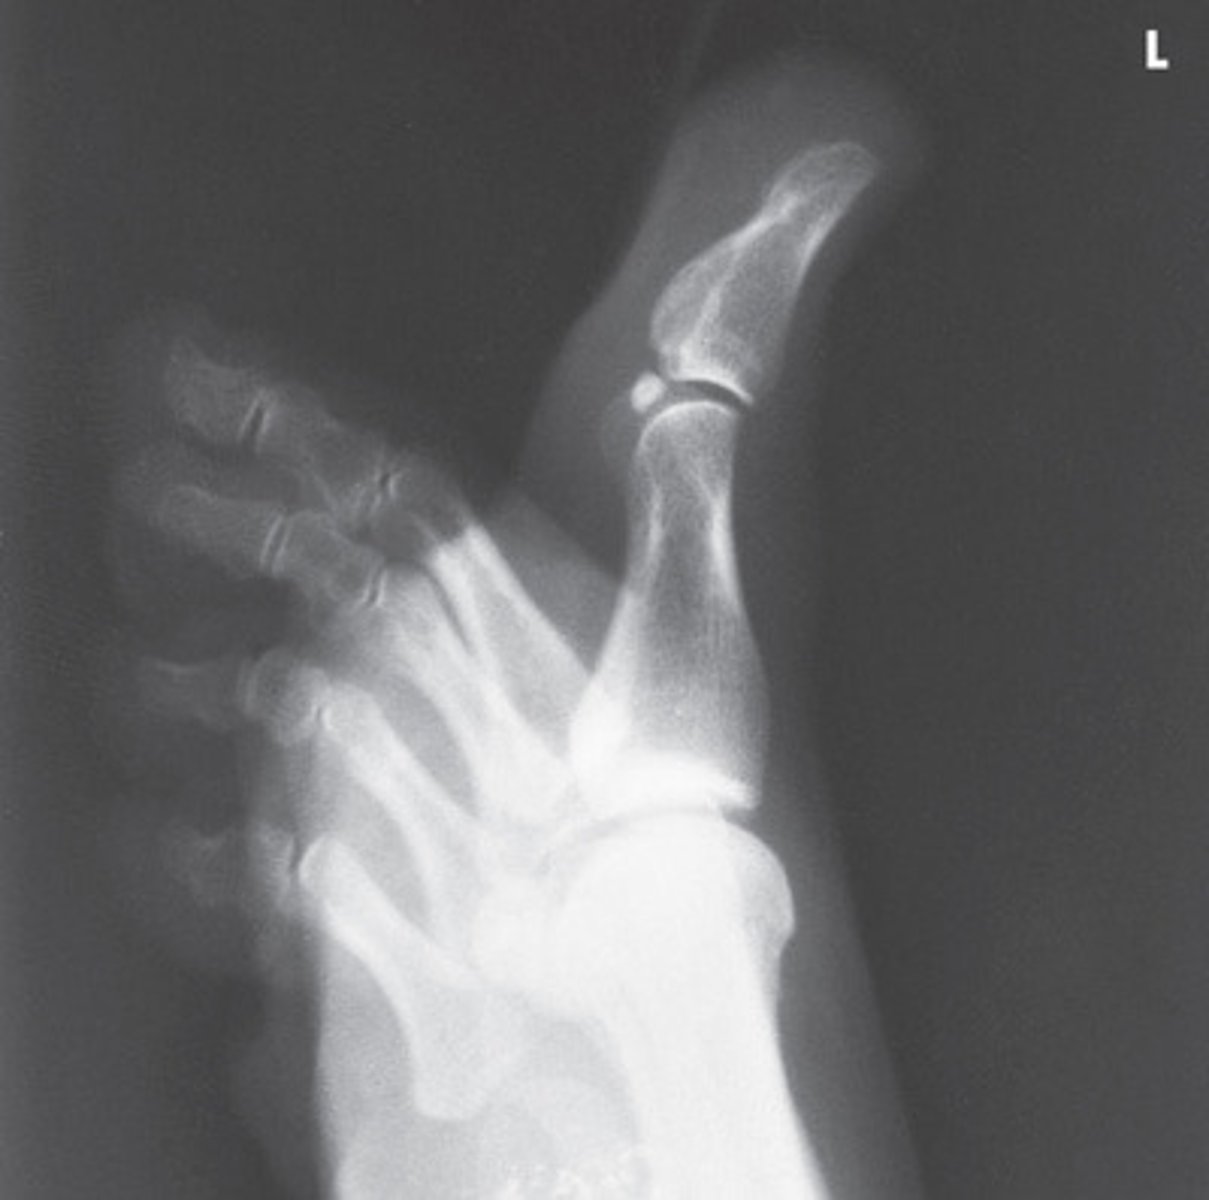

Lateral First Digit

What projection is this?

Evaluation Criteria for Lateral First Digit

- Lateromedial

- CR to IP

- Digits presented in true lateral position

- IP and MTP joints appear open

- Digit free of superimposition

- Optimal exposure factors